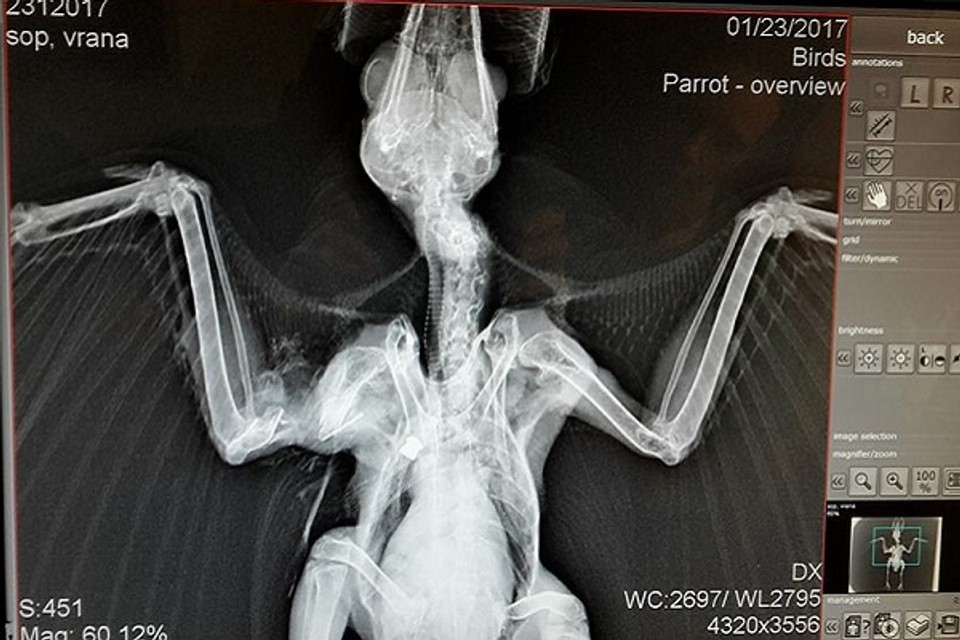

Opakované prípady zástrelu havranov a vrán z Vrakune. Táto vrana bola odchytená v jednej zo záhrad, odkiaľ nevedela vzlietnuť s podozrením na zlomeninu krídla. Röntgen však odhalil skutočnú príčinu,  uvádza na sociálnej sieti Regionálne centrum ochrany prírody Bratislava a Správa CHKO Dunajské luhy. Ochranári zverejnili aj röntgenovú snímku zraneného vtáka a upozorňujú, že všetky druhy vtákov s výnimkou holubov sú zákonom chránené.